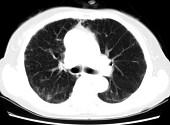

问题 女,35岁,咳嗽,咳痰,发热3月余,胸部CT如图,最可能的诊断为 ( )

选项 A.类风湿肺炎 B.红斑狼疮性肺炎 C.间质性肺炎 D.肺结节病 E.肺部感染

答案 C